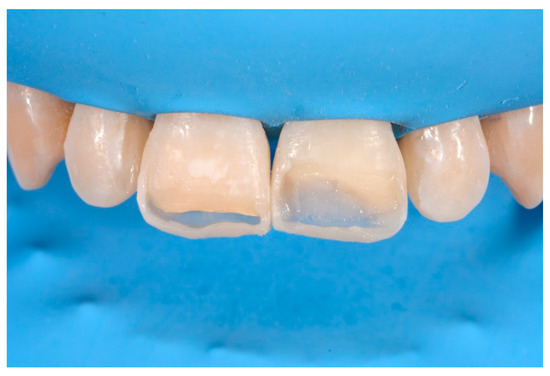

2.1.3. Completion of the Layering Procedure, Finishing and Polishing

A single shade of dentin (Clearfil Majesty ES-2, A1D, Kuraray Noritake Dental, Tokyo, Japan) was then applied placing separate increments (Figure 10 and Figure 11) to build the dentinal body, leaving space for incisal translucencies. The translucent shade (Clearfil Majesty ES-2, A1E, Kuraray Noritake Dental, Tokyo, Japan) was then applied to complete the restoration (Figure 12).

Figure 12.

Enamel layer applied. Reprinted from Restauri diretti nei settori anteriori, G. Paolone, S. Scolavino, © 2021, with permission from Quintessence Publishing Italy.